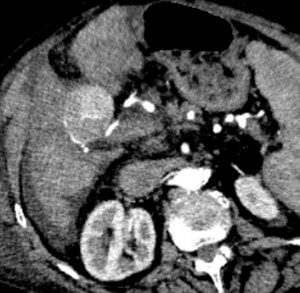

Pre-Procedure CTA

The pre-procedure CTA demonstrated a single hyper vascular mass within segment 4 supplied by an apparent single feeding branch of the right hepatic artery.